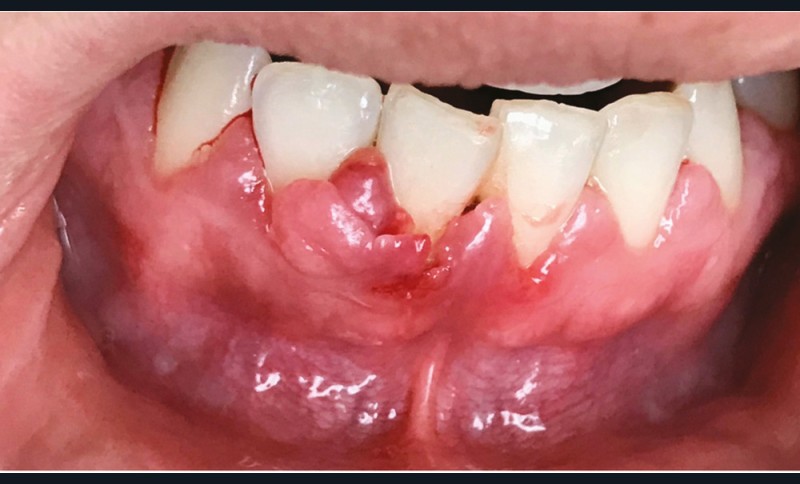

Les modifications hormonales à mettre en relation avec l’hygiène bucco-dentaire, les paramètres socio-économiques, l’âge précoce de la grossesse ainsi que l’augmentation du grignotage pourraient augmenter la prévalence des caries dentaires chez la femme enceinte. Ces patientes sont régulièrement sujettes à des envies multipliant le nombre de prises alimentaires souvent très riches en sucre. Ces apports sucrés, associés à la baisse du pH salivaire lors de la grossesse, entraînent un déséquilibre du cycle déminéralisation et de reminéralisation. Le risque carieux peut être augmenté, ainsi que la susceptibilité à l’érosion dentaire accrue par les vomissements et/ou les reflux gastro-œsophagiens [2]. L’action hormonale peut également avoir des répercussions sur les tissus parodontaux. La gingivite gravidique observée sur plus d’une femme enceinte sur deux, constitue une réponse inflammatoire de la gencive exacerbée par la présence de plaque bactérienne, et favorisée par l’augmentation des taux d’œstrogène et de progestérone [3] (fig. 1). 5 % des futures mères développeront un épulis, dont l’étiologie reste méconnue (fig. 2) [4].